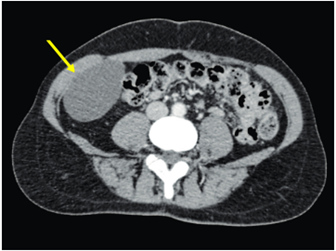

Se realizó ecografía abdominal visualizándose masa hipoecogénica en fosa ilíaca derecha, de contornos bien definidos, inmediatamente anterior al músculo psoas derecho. En la tomografía computarizada (Figura 1) y en la resonancia magnética (Figura 2) de abdomen se observó una lesión de densidad quística, de localización aparentemente extracompartimental en íntima relación con músculo transverso del abdomen derecho, que desplazaba el colon ascendente.